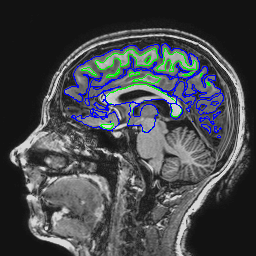

The following images show a T1 image with outlines for the outer boundary of gray matter (blue line) and white matter (green line).

Here are corrected EPI images with the gray and white matter boundaries overlaid.